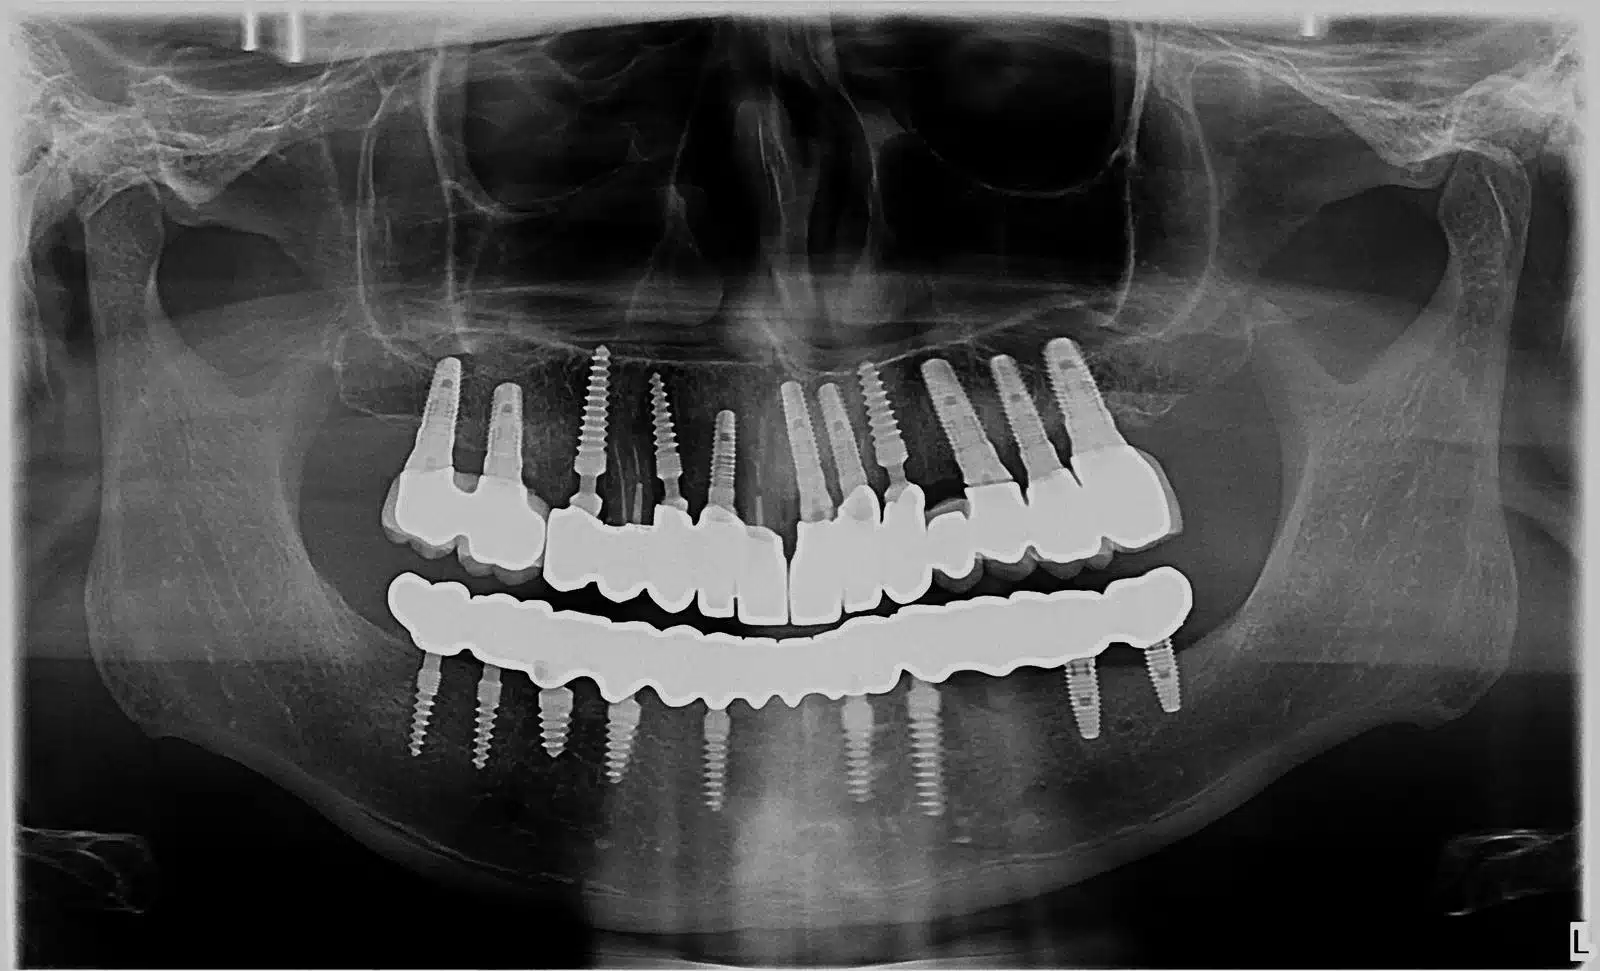

Day 1–2: Full Examination & Digital Design

✓ facial scans

✓ intraoral scanning

✓ panoramic or 3D imaging

✓ smile simulation preview

- share panoramic X-ray if available